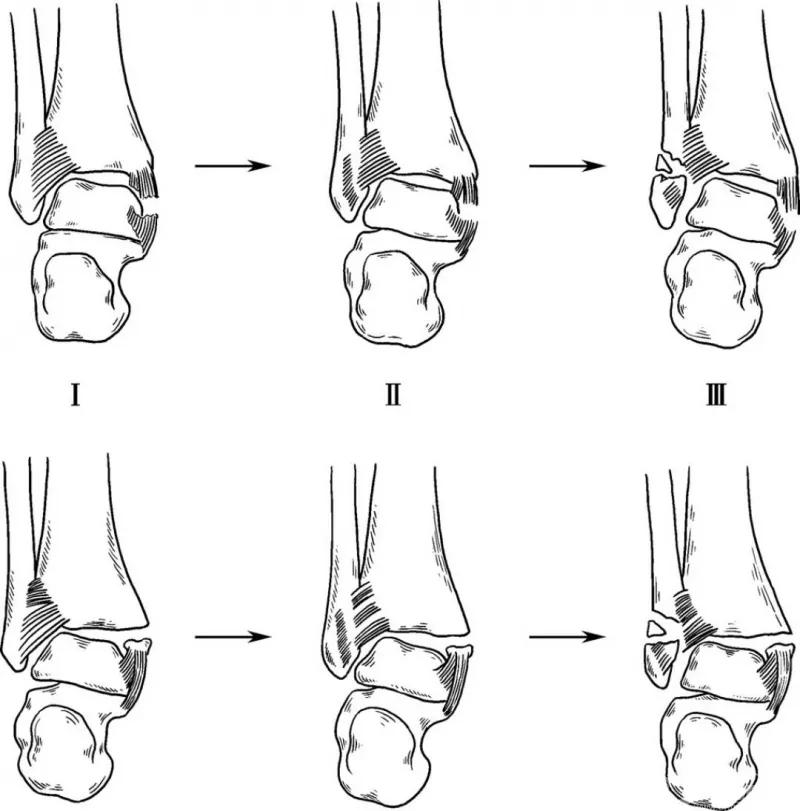

1. 旋后—内收型

旋后是指距下关节内翻、胫距关节内旋和前足内收,此时第一跖骨及足心朝向头侧,第五跖骨向尾侧。此位置时踝外侧结构绷紧,在旋后和内收外力作用下,首先会造成外侧副韧带断裂或发生外踝撕脱骨折、横形骨折。骨折在下胫腓联合韧带下方,下胫腓韧带仍保持完整。进一步的内收距骨撞击关节内侧,结果造成与距骨内角垂直的骨折线,有时会造成胫骨远端内侧关节面压缩,也可能造成距骨软骨下压缩性骨折。旋后—内收型骨折分两度(图1)。

图1 旋后—内收型

3. 旋前—外展型

足旋前时,踝内侧结构紧张并损伤,三角韧带损伤或内踝撕脱骨折,外展外力使下胫腓联合韧带断裂或结节撕脱骨折,外踝骨折线在下胫腓联合上方伴骨间膜断裂。外踝骨折为斜形或部分横断伴粉碎性或伴楔形骨块。旋前—外展型骨折分三度(图3)。

图3 旋前—外展型